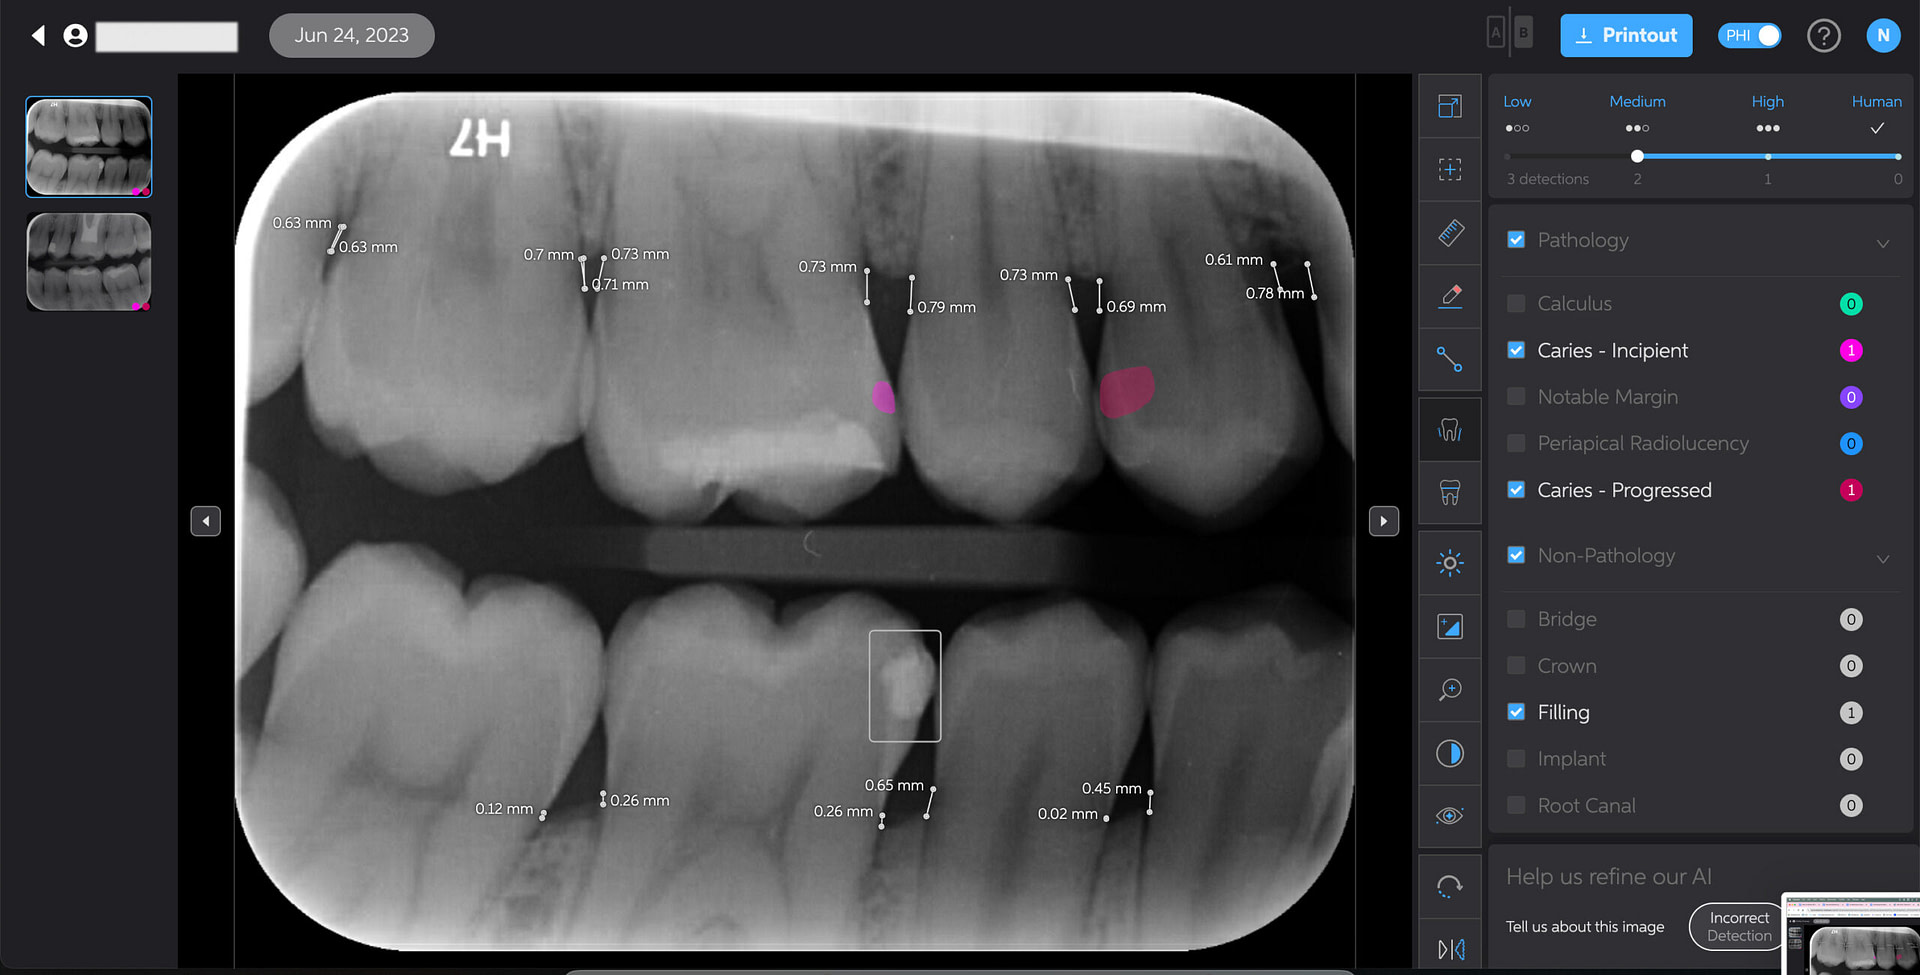

Bone Measurements

The system provides automated measurements from the crest of the bone to the cementoenamel junction (CEJ). These measurements are color-coded to indicate severity:

- White: 0-2.5 mm

- Yellow: 2.5-4 mm

- Amber: >4 mm

This feature is helpful for periodontal assessments, streamlining the process of identifying areas of bone loss. However, it's important to note that image angulation can affect the accuracy of these measurements, a limitation the system acknowledges.

I found these lines to be incredibly useful when describing patients' periodontal health. Cool feature, no doubt.

Caries Detection

The best for last and arguably the most well-thought-out feature. Especially with the tooth segmentation mode, which makes it easier for patients to understand their diagnosis and treatment plans.

The system uses two shades of pink to indicate potential caries:

- Light pink: Incipient caries (100% in enamel) - we will often review

- Darker magenta: Caries extending into dentin - we need to restore

The system even provides a percentage breakdown of enamel vs. dentin involvement. I have been blown away by its accuracy while using it, and it makes something that feels quite subjective (reading shades of grey) into a science.